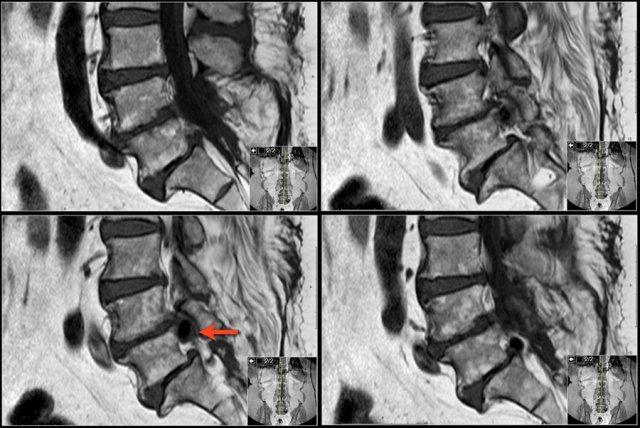

Ngoài ra còn có rách vòng sợi (tăng tín hiệu) là nơi đĩa đệm thoát vị qua (mũi tên vàng). - Tại mức ngách bên, có thoát vị khu trú của chất đĩa đệm gây chèn ép rễ thần kinh L5 (mũi tên vàng).

Đây được gọi là thoát vị thực sự (extrusion), vì khoảng cách giữa các bờ của khối thoát vị lớn hơn khoảng cách tại nền. - Rễ thần kinh L5 bị chèn ép (mũi tên xanh dương) trong ngách bên.

Đĩa đệm thoát vị đã di trú xuống phía dưới và được thấy như một cấu trúc hình bầu dục nằm phía trước rễ thần kinh.

Đĩa đệm thoát vị không được bao bọc, tức là không được che phủ bởi các sợi của vòng sợi.